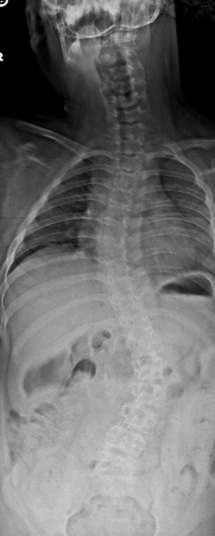

Skeletal problems are common in BBS and should be discussed with your doctors. The skeletal issues range from extra fingers and toes (polydactyly) to club feet to hip disease (hip dysplasia) with differences in the length of the legs. Some people have extra/missing ribs and in adults spinal stenosis may be a problem. One important issue that can be easily overlooked is scoliosis. Scoliosis is an abnormal curvature of the spine. Unfortunately, it cannot always be picked up by a physical examination especially if your health care providers do not carefully examine the back. Scoliosis often develops in childhood and may require bracing or surgery. In the attached x-ray scoliosis is shown with curves in the spine in the chest and in the mid-abdominal area. Please be sure to discuss scoliosis with your doctors and make sure the best care possible is rendered.